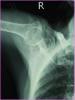

患者女,72岁,诊断为:肱骨近端骨折。

行肱骨近端锁定型钉板(PHILOS)固定术,手术过程:采用全麻或斜方肌阻滞麻醉,用沙滩椅体位,术中肱骨头复位后,用二至三枚克氏针临时固定保持复位,并使其余骨折块复位,然后透视确认复位质量。用5号不可吸收缝线将大小结节缝合修复,再选用适当长度的锁定钉板置于肱骨近端和肱骨干的外侧面。注意避免将钢板放置的过高以致成角螺钉的位置不合适而不能达到最佳骨接触。可用一枚非锁定螺钉固定于肱骨干上可使钢板远近端滑动调整位置。然后使用导向器上锁定螺钉使钢板和螺钉一体化。固定完成后再次透视确认无误,处理好软组织后逐层关闭切口。